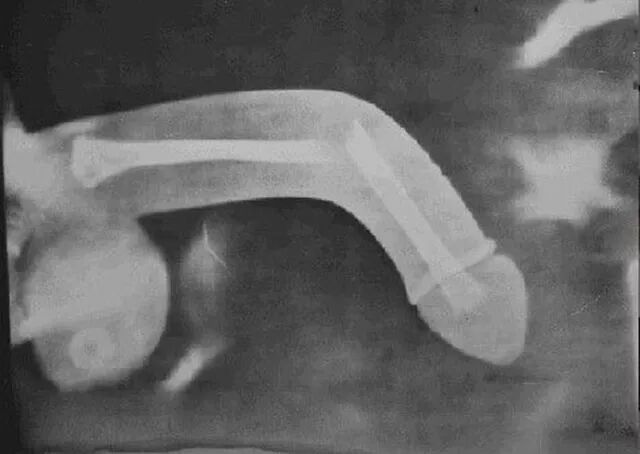

临床上,阴茎充分勃起后,由于姿势不当,或用力过猛等巧合因素,也可能导致另外一种急诊,俗称「阴茎骨折」。阴茎内没有骨性结构,骨折无从谈起,实际上专业术语称之为「海绵体白膜破裂」。

阴茎勃起时,大量血液灌注进入海绵体,而海绵体外有一层坚韧的膜状结构,导致有限空间内压力上升,外观看来就是阴茎变硬、勃起。性生活中采取不当体位,可能形成白膜处剪切应力增加,超过一定限度可导致白膜破裂。

白膜破裂后,海绵体内血压在强大压力的作用下,快速流出,阴茎血肿,体积增大,质地变软,因血液溢出后回流不畅,含氧量下降,逐渐成暗红色,甚至青紫色,患者就诊时常将其描述为「大紫茄子」。文章开头那则新闻中讲的「爆炸」应该就是这种情况吧。